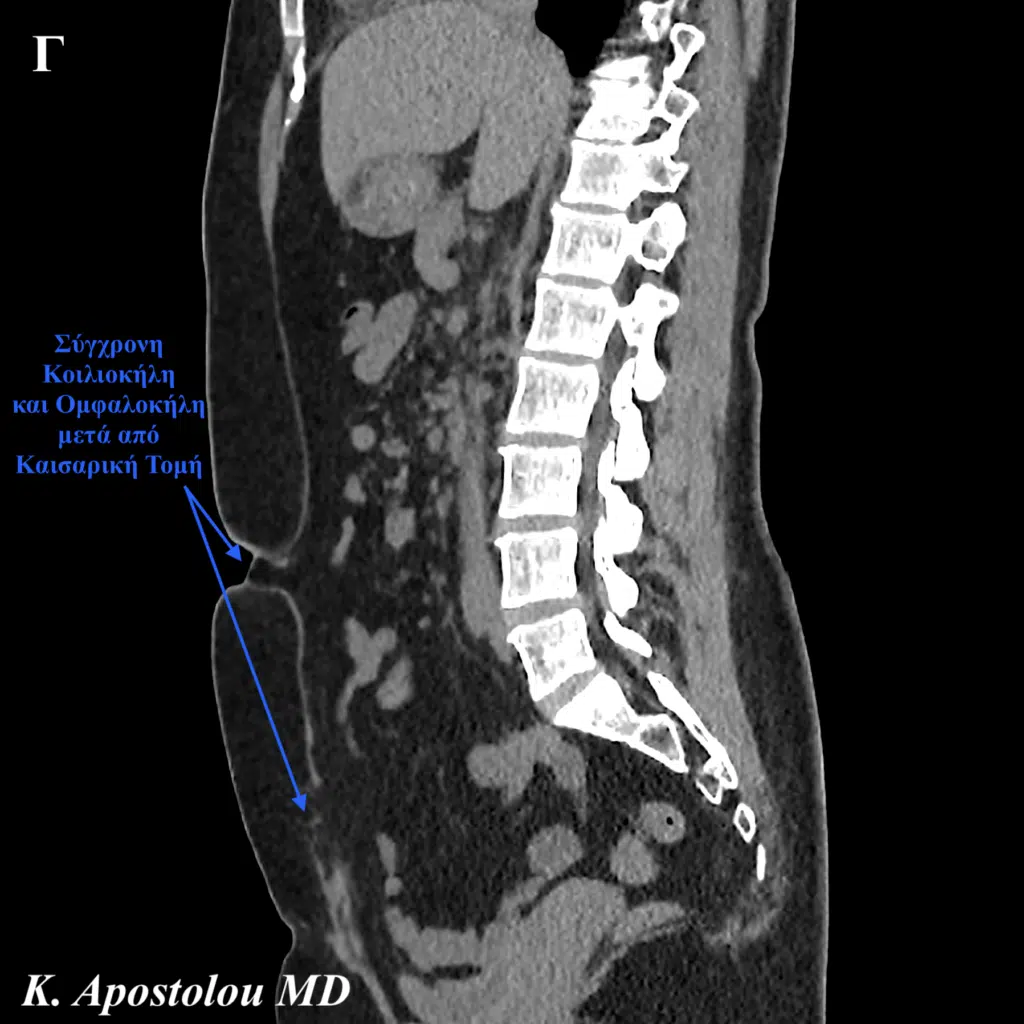

Η κλινική εξέταση της ασθενούς πραγματοποιήθηκε με την ασθενή τόσο σε ύπτια θέση όσο και σε όρθια στάση του σώματος, αποκαλύπτοντας:

- Κήλη μετά από καισαρική τομή, με σύγχρονη

- Ομφαλοκήλη μετά από καισαρική.

Η κλινική διάγνωση επιβεβαιώθηκε με την πραγματοποίηση αξονικής τομογραφίας άνω και κάτω κοιλίας, η οποία ανέδειξε την παρουσία μίας κήλης στην καισαρική τομή διαστάσεων 6.5 x 2.5 cm καθώς και μίας σύγχρονης ομφαλοκήλης διαστάσεων 1.9 x 1.4 cm.

Η ασθενής ενημερώθηκε ενδελεχώς για την δυνατότητα σύγχρονης χειρουργικής αποκατάστασης τόσο της κήλης μετά από καισαρική όσο και της ομφαλοκήλης με την εφαρμογή ελάχιστα επεμβατικών χειρουργικών τεχνικών (λαπαροσκοπική μέθοδος) και μερικές ημέρες αργότερα οδηγήθηκε στο χειρουργείο.